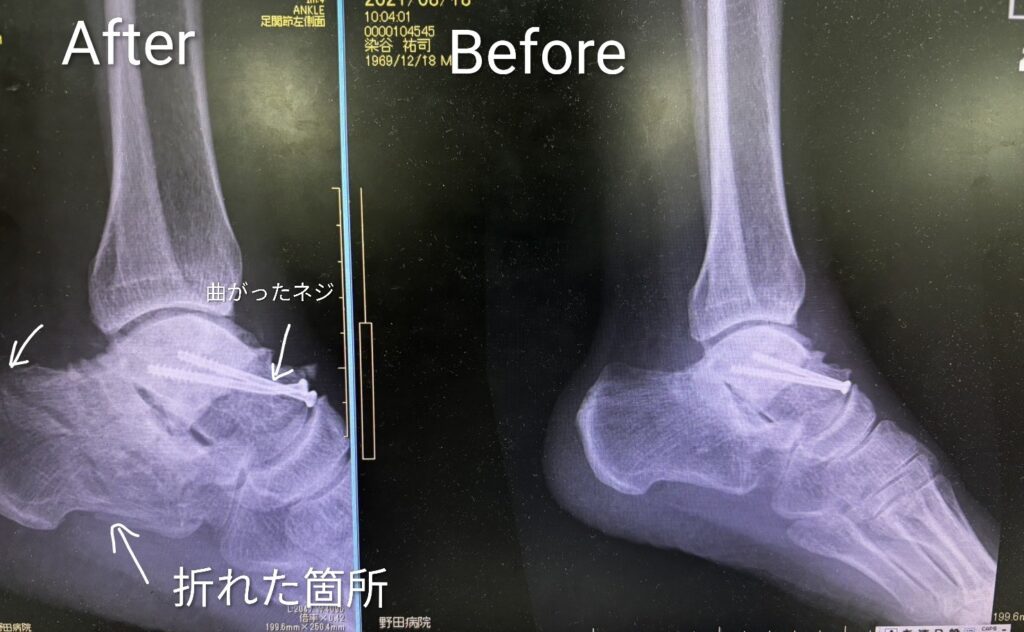

しかし今回は、距骨に入っているチタンネジの2本のうちの1本が衝撃で曲がってました。

いやぁ〜距骨が外れなくて良かったです。